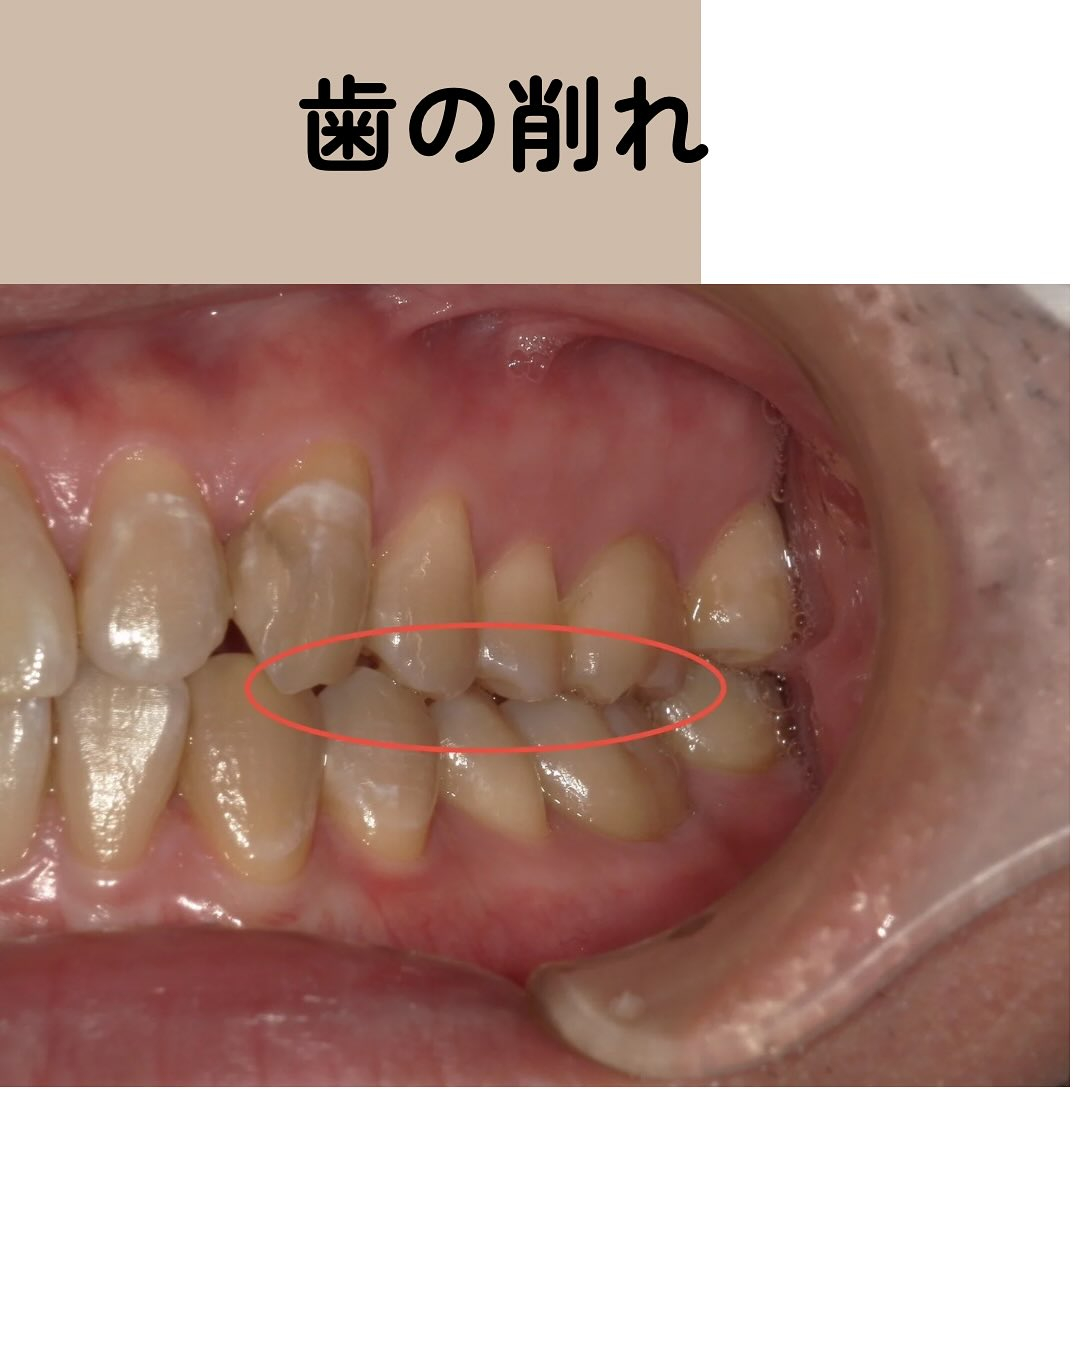

③、④、⑤に関しては当院の患者さんの症例画像をお見せします👀

③は主に就寝時の歯ぎしりにより生じ、歯同士の擦れ合いによるものです👀